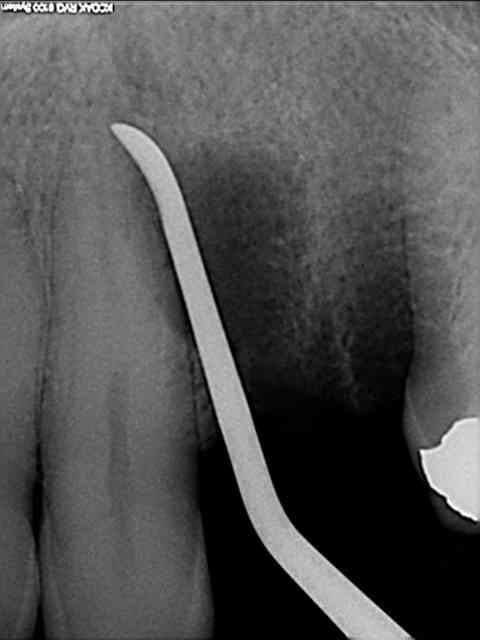

tiens voici des photos de ce matin...

patient avec kyste +++ aux apex et fenestration

je n'implante pas

je comble au Graftec

je met une membrane

je referme

8 mois après,

je vais implanter

comme je suis curieux, j'ouvre large et je regarde;

c'est décevant,le volume est là mais l'os n'est pas génial.

voilà pour les photos...

pendant que je forais, et le patient le sentait également, je sentais et entendais les particules de graftec.

en plus au bout de 8 mois j'aurai espéré trouver quelque chose de mieux non ?